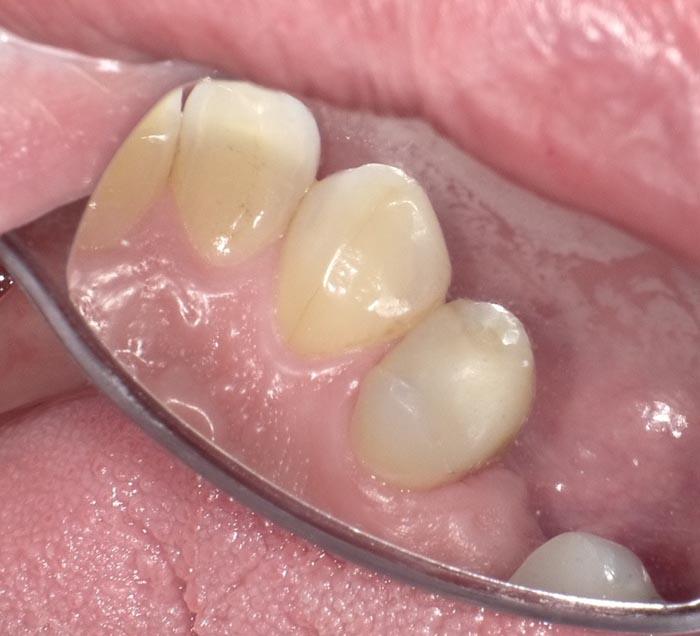

A 37-year-old patient presented for treatment after years of neglect. After administering anesthetic and placing an Isolite isolation device, we prepared teeth #10–12 and restored them

with Activa Bioactive-Restorative composite.

• Figure 3